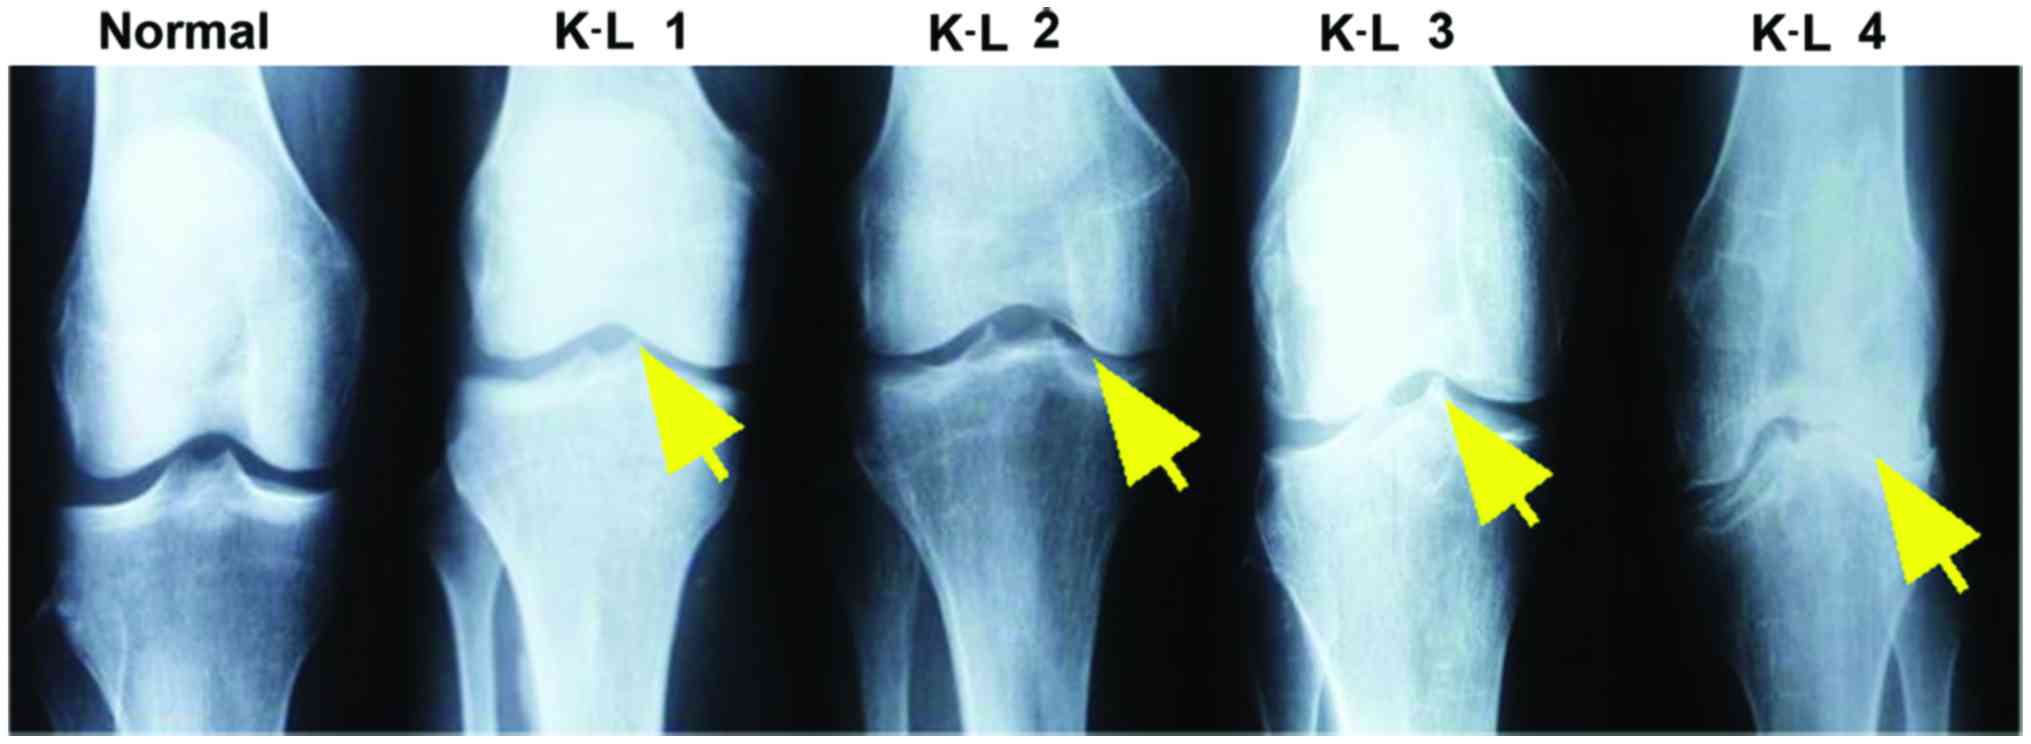

Kellgren-Lawrence Grade는 위의 표와 같습니다.

Grade를 각각 자세히 보게되면

0은 정상

1은 JSN(joint space narrowing)나 작은 골극이 생길수 있고 (fibrillation, disruption)

2부터는 JSN 가능성이 1보다 높아지고, 명확한 골극이 관찰됩니다.

3부터는 여러 골극과, 중등도 JSN와, 뼈의 변형, 연골하골 경화의 관찰이 있을 수 있습니다.

마지막 단계인 4의 경우 큰 골극과, 매우 명확한 JSN, 심한 연골하골 경화, 뼈의 심한 변형 등이 있을 수 있습니다.

아래 여러 사진을 보면서 한번더 확인해보면 0에서 4로가면서 관절간격도 좁아지며, 골극과, 뼈의 변형이 더 심해지는 것을 알 수 있습니다.

인공 관절은 K-L grade 4부터 이며, 임상적인 치료는 grade 2부터 시작할 수 있습니다.